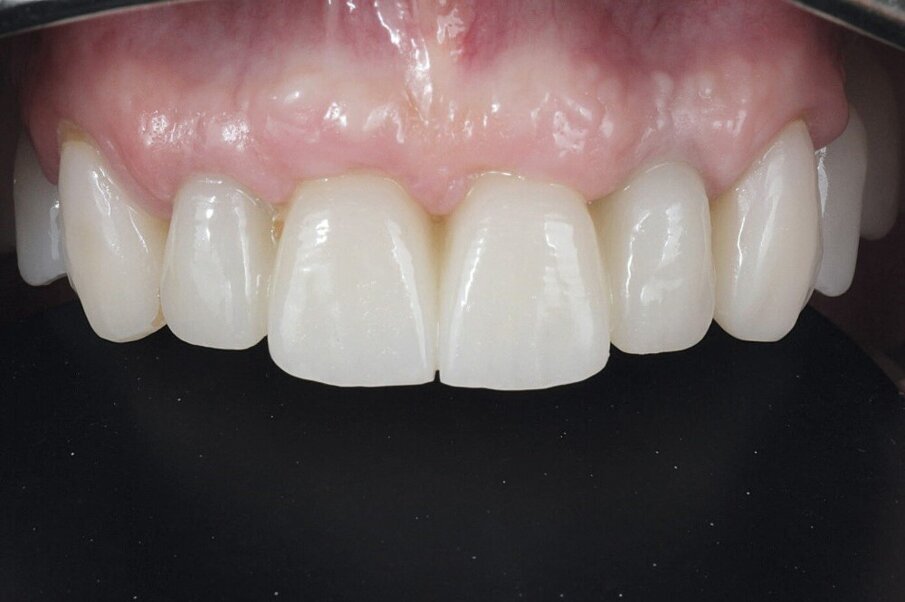

Definitivni protetski rad napravljen je nakon što je završila faza oseointegracije implantata s tri monolitna mosta od cirkonijevog dioksida (DD CubeX, Dental Direkt) proizvedenih CAD/CAM postupkom. Mostovi su pomoću vijaka pričvršćeni na titanske abutmente (PS TiB, BEGO Implant Systems) (Slike 14–16). Pravilan dosjed protetske nadogradnja se nakon umetanja potvrdio rendgenskom snimkom (Slika 17.). Kontrolni pregled nakon dvije godine u srpnju 2019. pokazao je izvrsno estetsko i kliničko stanje mekog tkiva (Slike 18–20). U području implantata radiografski se nije mogao utvrditi gubitak krestalne kosti (Slika 21.). Oba korijena središnjih sjekutića koji su ostavljeni u alveoli kao ni distobukalni korijen zuba 26 nisu pokazali nikakve znakove periapikalne upale. Pacijentica nije imala nikakvih pritužbi, a oralna higijena značajno se poboljšala tijekom razdoblja praćenja.

Slika 14. Frontalni prikaz definitivne protetske nadogradnje. Odnosi pokazuju dobru estetiku bez znakova komplikacija mekih tkiva Slika 15. Pogled na definitivni rad s desne strane. Slika 16. Pogled na definitivni rad s lijeve strane. Slika 17. Završna rendgenska slika s definitivnim implanto protetskim radom in situ. Slika 18. Frontalni prikaz definitivnog protetskog rada nakon dvogodišnjeg praćenja. Slika 19. Prikaz definitivnog protetskog rada s lijeve strane nakon dvogodišnjeg praćenja. Slika 20. Prikaz definitivnog protetskog rada s desne strane nakon dvogodišnjeg praćenja.